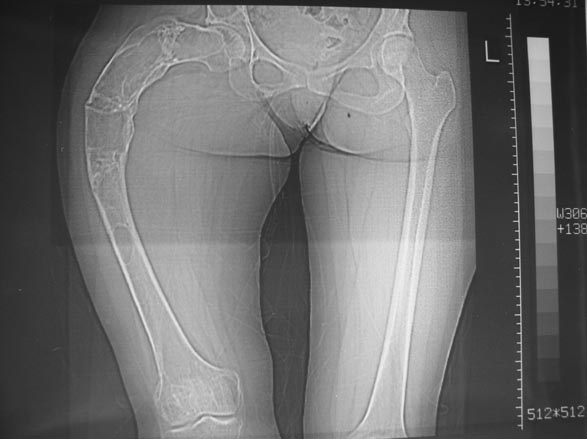

В ноябре этого года я обращался с просьбой о помощи в выборе тактики лечения больной с деформацией бедра на почве фиброзной дисплазии. Были получены интересные и очень полезные советы по операции.

Операция выполнялась с помощью А.Н.Челнокова. Очень понравилась технология выполнения блокируемого остеосинтеза с использованием спицевого дистрактора, модифицированный гвоздь с латерализованным проксимальным отделом и возможностью многовинтовой фиксации проксимального и дистального участков бедра.